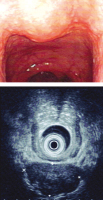

Abbildung 1: Endoskopischer und endosonographischer Aspekt des SMT 2005

Endoskopie

Endosonographie

Onkologie

SMT

submukosaler Tumor

Abbildung 5: OP-Situs 12/2012

Foto

OP-Situs